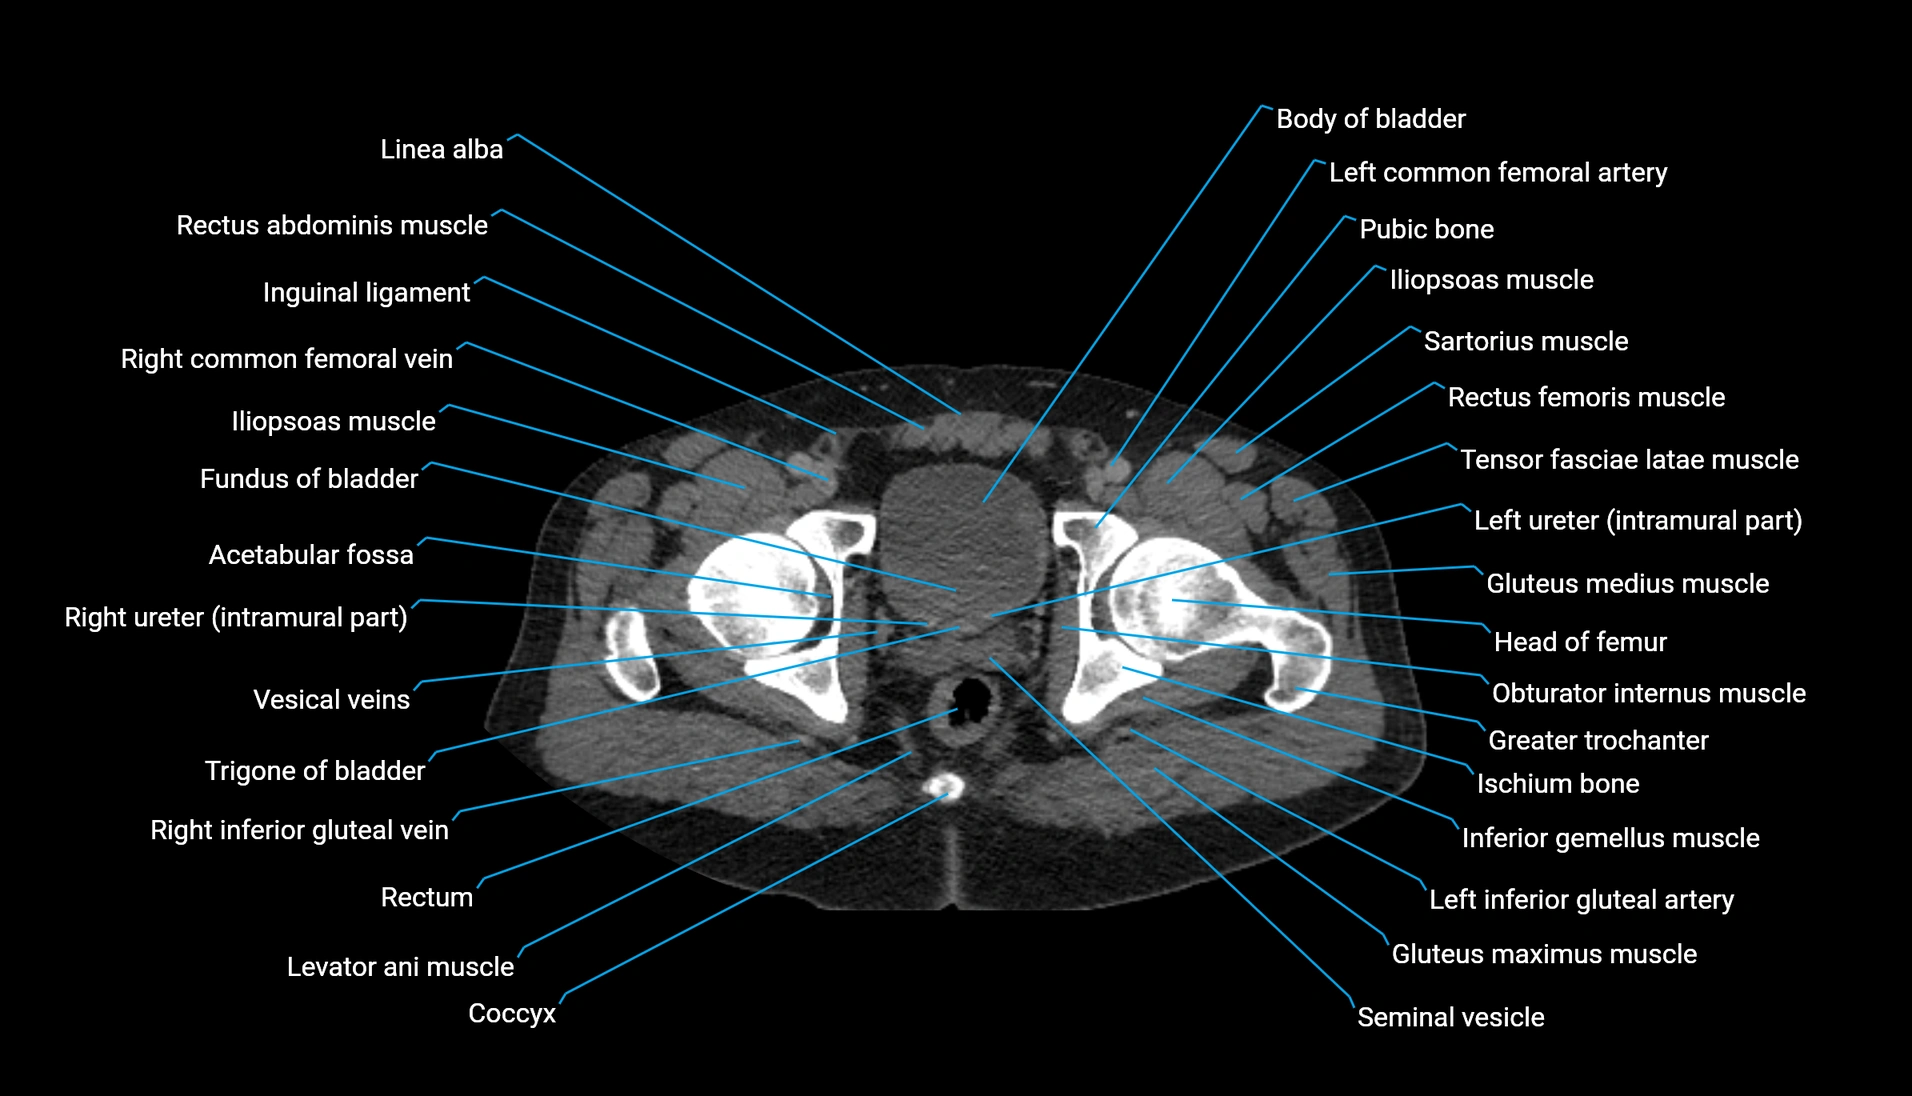

CT Appearance

Non-contrast CT:

-

Demonstrates cortical bone of acetabular rim in excellent detail

Detects fractures, dysplasia, retroversion, or bony overcoverage (pincer impingement)

3D reconstructions used in preoperative hip surgery planning

CT VRT 3D image

CT image